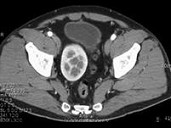

- 单项选择题男,27岁, 根据所示图像,最可能的诊断是 ( )

A、盆腔肾

B、腰段肾

C、胸内肾

D、肾下垂

E、游走肾